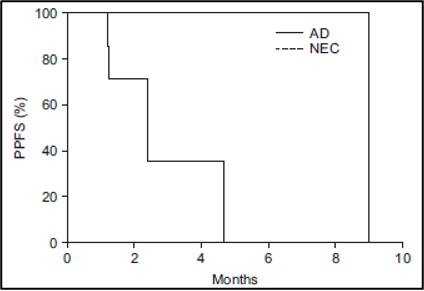

נפח כבד שלם (Whole liver volume) גדול מ-3,000 מ"ל (p = 0.02) (איור 5B), אשר ייצג בעקיפין נפח גידול גרורתי (metastatic tumor volume), היה קשור באופן מובהק להישרדות ללא התקדמות כאב (PPFS) נמוכה יותר. הישרדות ללא התקדמות כאב (PPFS) נוטה להיות גבוהה יותר במטופלים עם קרצינומה נוירואנדוקרינית (neuroendocrine carcinoma) (p = 0.11) (איור משלים 2) ורמה ראשונית של אנטיגן קרצינואמבריוני (CEA) גבוהה מ-50 ננוגרם/מ"ל (p = 0.12) (איור משלים 3). תגובה אובייקטיבית (Objective response) לאחר חודש אחד לא הייתה קשורה להישרדות ללא התקדמות כאב (PPFS) (p =0.43).

איור משלים 2: עקומת ההישרדות של קפלן-מאיר של ההישרדות ללא התקדמות כאב (PPFS) בהתאם לפתולוגיה של הגידול הראשוני

איור משלים 3: עקומת ההישרדות של קפלן-מאיר של ההישרדות ללא התקדמות כאב (PPFS) בהתאם לרמה הראשונית של האנטיגן הקרצינואמבריוני (CEA)